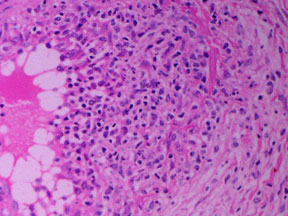

Blood vessels: